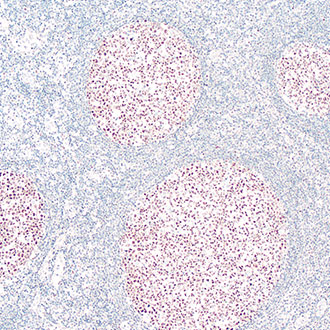

Ki-67

Ki-67 -